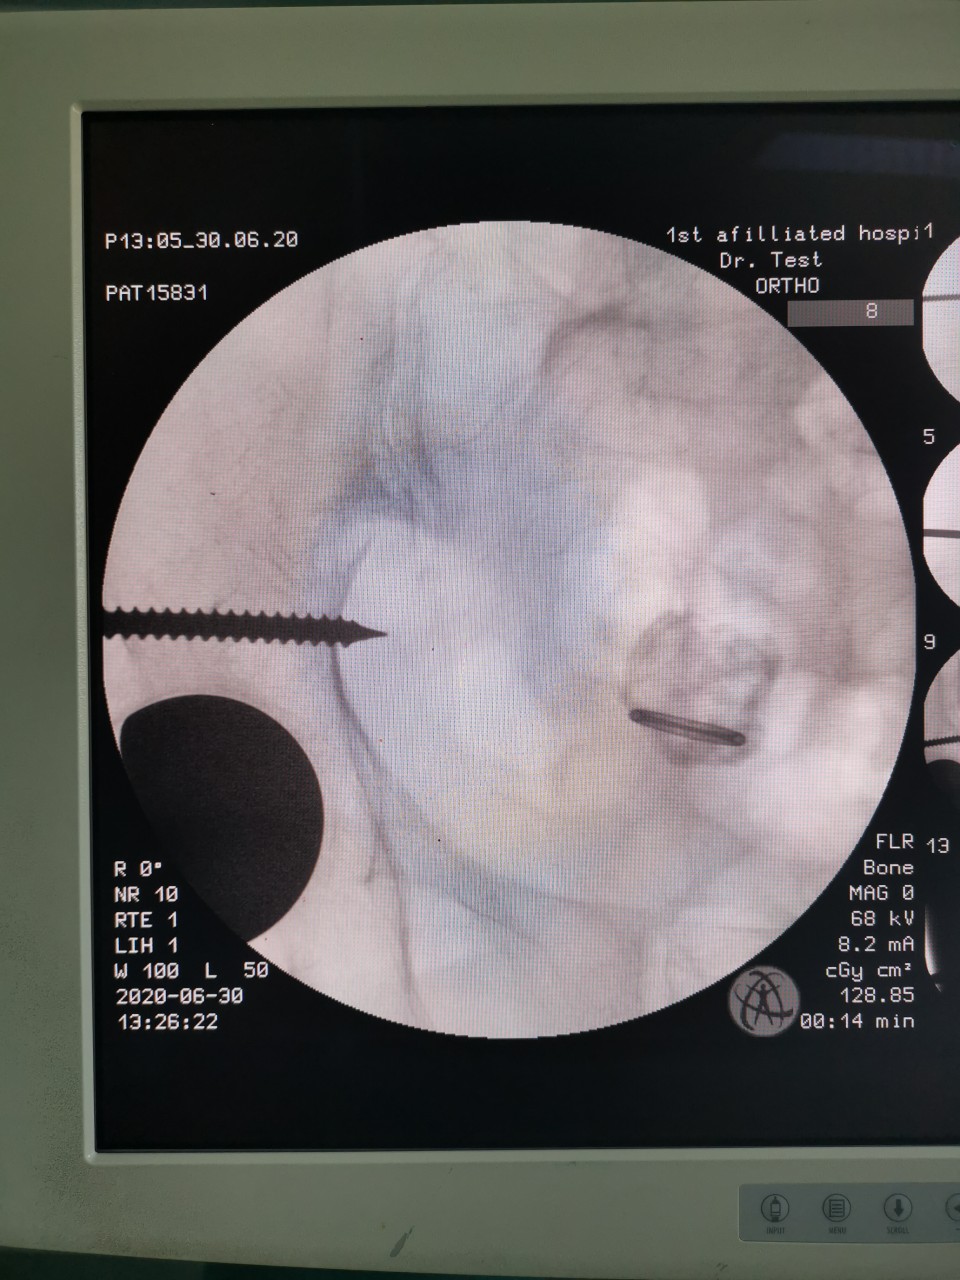

术中透视

患者女,81岁,既往曾因股骨颈骨折行右髋关节置换术,此次入院当天因外伤致髋部周围疼痛及活动受限入住我院创伤骨科。经术前检查及评估,诊断为“骨盆骨折”。对于此例高龄骨盆骨折患者,王刚副主任医师团队决定为其施行“闭合复位微创内固定手术”,手术用时仅30分钟,在闭合复位后,通过3枚骨盆通道螺钉固定骨折部位,基本无手术出血,术后两天患者恢复良好,予以出院。